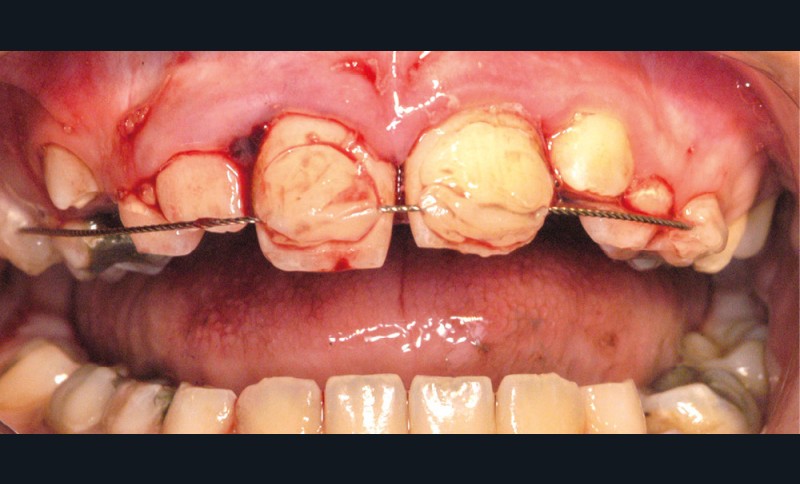

Enfant de 9 ans dont une incisive centrale maxillaire a été expulsée en jouant au football. Appel immédiat de la mère à qui l’on conseille de conserver la dent expulsée dans du sérum physiologique (fig. 1). Le temps extra-alvéolaire à sec a été inférieur à 5 minutes. Le patient arrive 40 minutes après le traumatisme dans l’Unité d’Odontologie pédiatrique. Après interrogatoire, examen clinique et radiographique, un rinçage de l’alvéole est effectué et la dent est réimplantée le plus rapidement possible (fig. 2). Une contention semi-rigide est ensuite placée (fig. 2). La dent étant mature, la prise en charge endodontique (séance de Ca(OH)2 puis obturation à la gutta percha) débute deux semaines plus tard (fig. 3 et 4) afin de limiter les risques d’infection, de résorption. Le suivi sur quatre années montre une dent fonctionnelle, sans ankylose ni résorption radiculaire ou osseuse.